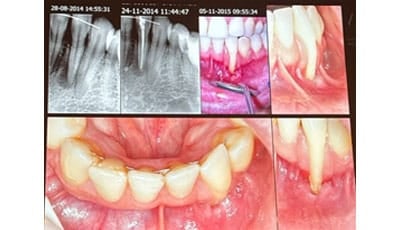

Het tandvleesrandje: minimaal invasief

Wanneer we spreken over minimaal invasieve tandheelkunde, is dit een breed begrip. Maar volgens Giles de Quincey moeten we het ook hebben over interdisciplinair werken, want we doen het niet alleen. Wat kan de parodontoloog betekenen voor een endodontoloog? En wat kan een parodontoloog bijdragen aan het werk van een orthodontist? Lees het verslag van zijn lezing tijdens MINIMAAL INVASIEF.